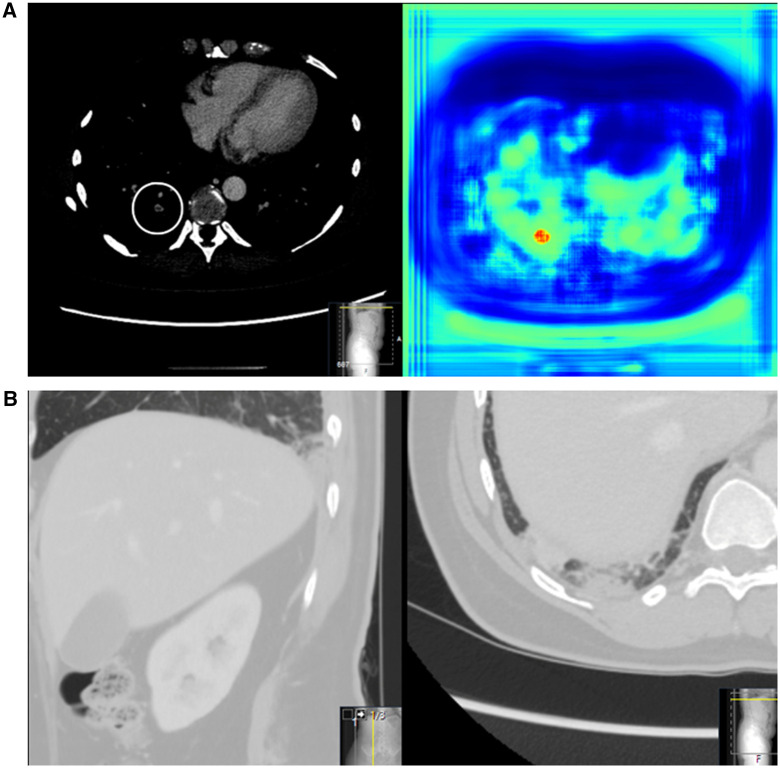

Abstract Image